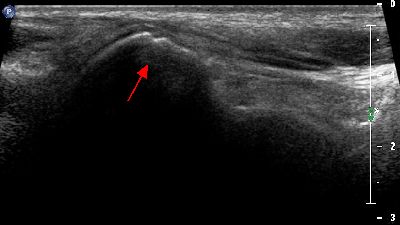

Pannicolo fibrotico intrarticolare

(caso del paziente A.C.)